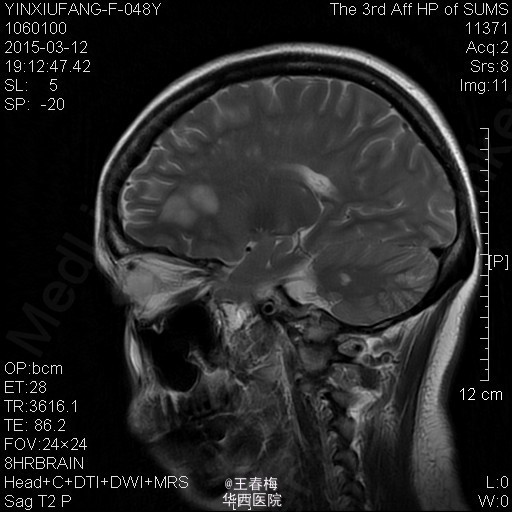

查体:神清,言语清晰,语速减慢,对答切题,检查合作,双侧瞳孔等大等圆,直径约3mm,瞳孔对光反射存在,眼裂正常,鼻唇沟无变浅,伸舌无偏斜,示齿口角无偏斜,双侧咽反射正常,双侧粗测视力、听力正常,四肢肌力、肌张力正常,双下肢病理征阴性。颈软,脑膜刺激征阴性,快速轮替试验、跟膝胫试验可疑阳性。辅助检查:血常规:白细胞总数3.270x10E9/L,淋巴细胞绝对值0.850x10E9/L。生化全套:高密度脂蛋白胆固醇0.350mmol/L,球蛋白24.800g/L。红细胞沉降率36.00mm/H。C反应蛋白10.200mg/L。体液免疫:补体40.420g/L,血清总补体86.000U/ml。元素六项:锌10.700umol/L,铁10.400umol/L。心肌酶谱:乳酸脱氢酶304.000U/L,磷酸肌酸激酶21.000U/L,α-羟丁酸脱氢酶257.000U/L。头颅MRA平扫+增强+脑功能成像:1、双侧额叶、顶叶、颞叶、放射冠、半卵圆中心、侧脑室旁、胼胝体、丘脑及小脑半球多发病灶,考虑脱髓鞘可能性大,其中部分病灶为活动期。2、头颅MRA脑动脉未见异常。3、双侧筛窦及上颌窦炎症。2015-03-18行腰椎穿刺术,脑脊液生化:脑脊液糖4.320mmol/L,脑脊液蛋白0.890g/L。生化八项:糖9.100mmol/L。神经元特异性烯醇化酶20.740ng/ml。MMSE评分11分。

诊断:多发性硬化。 处理:予止晕、营养神经治疗,2015-03-16起予甲强龙1g,qd静脉滴注连续冲击5天,后逐渐减少甲强龙用量。3-27复测MMSE评分为17分。